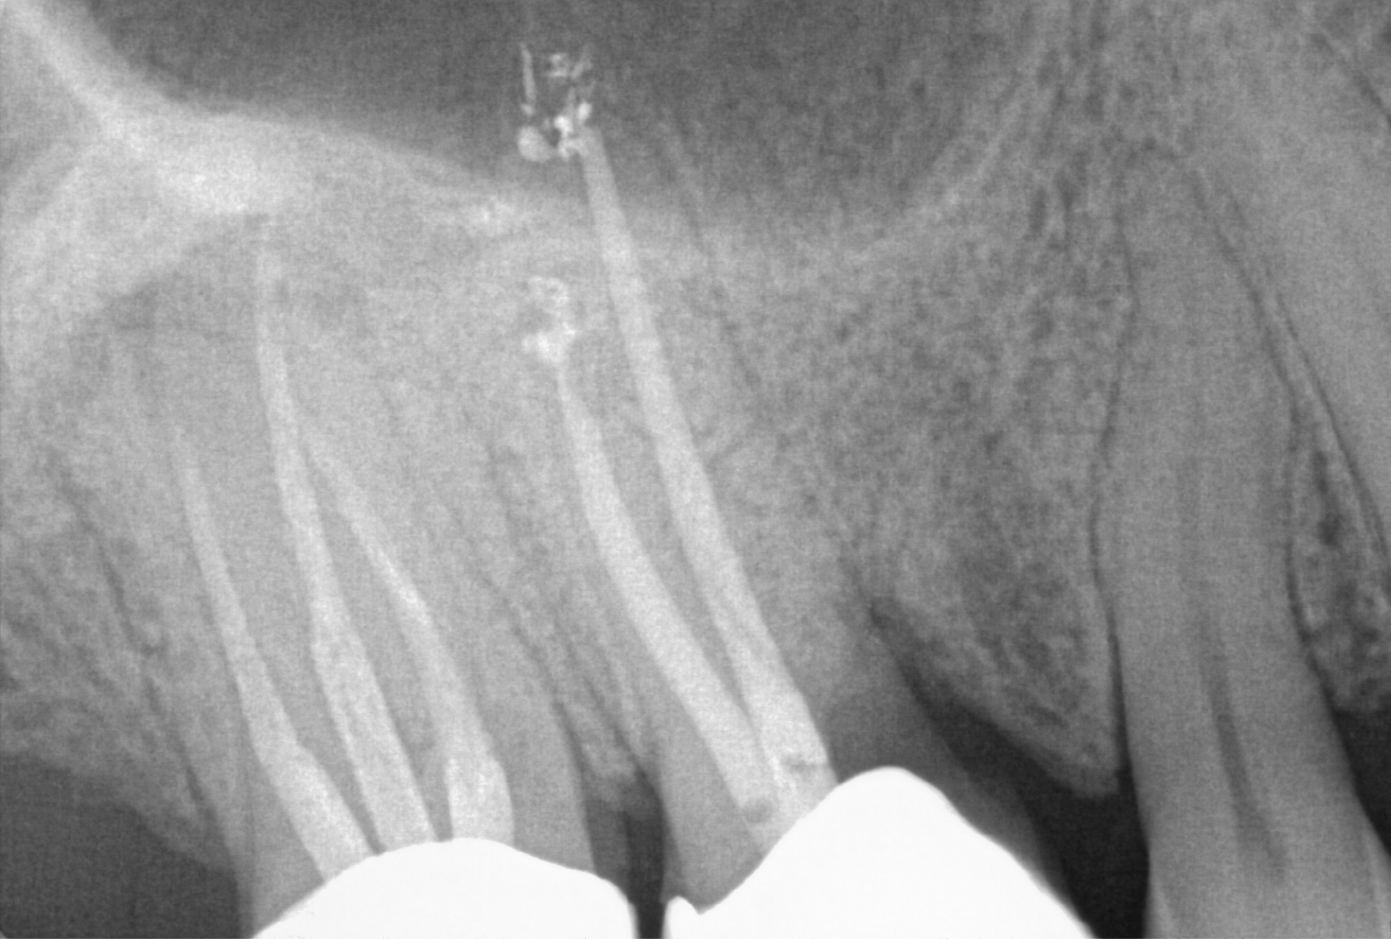

Traumatic Dental Injuries

Dental injuries can happen due to accidents or sports and range from minor chips to more serious problems like dislodged or knocked-out teeth. Endodontic treatment is crucial in these situations to save and protect the injured teeth. It's important to seek treatment quickly to avoid infection and other complications. Timely care can ensure the affected teeth are preserved and continue to function properly.